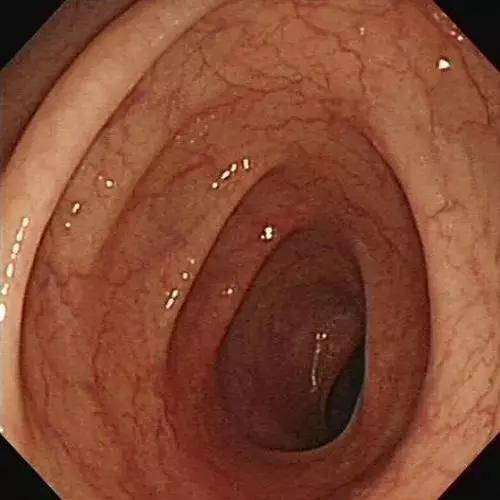

▲正常人的结肠